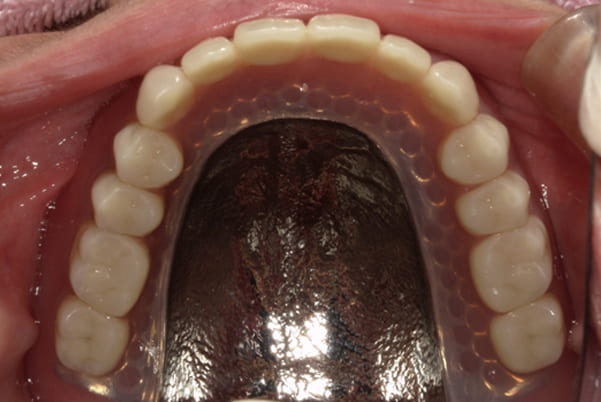

-

上顎治療後